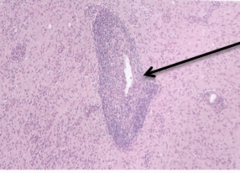

Granuloma

Front

central Core contains irritant and it is surrounded by chronic inflammatory cells